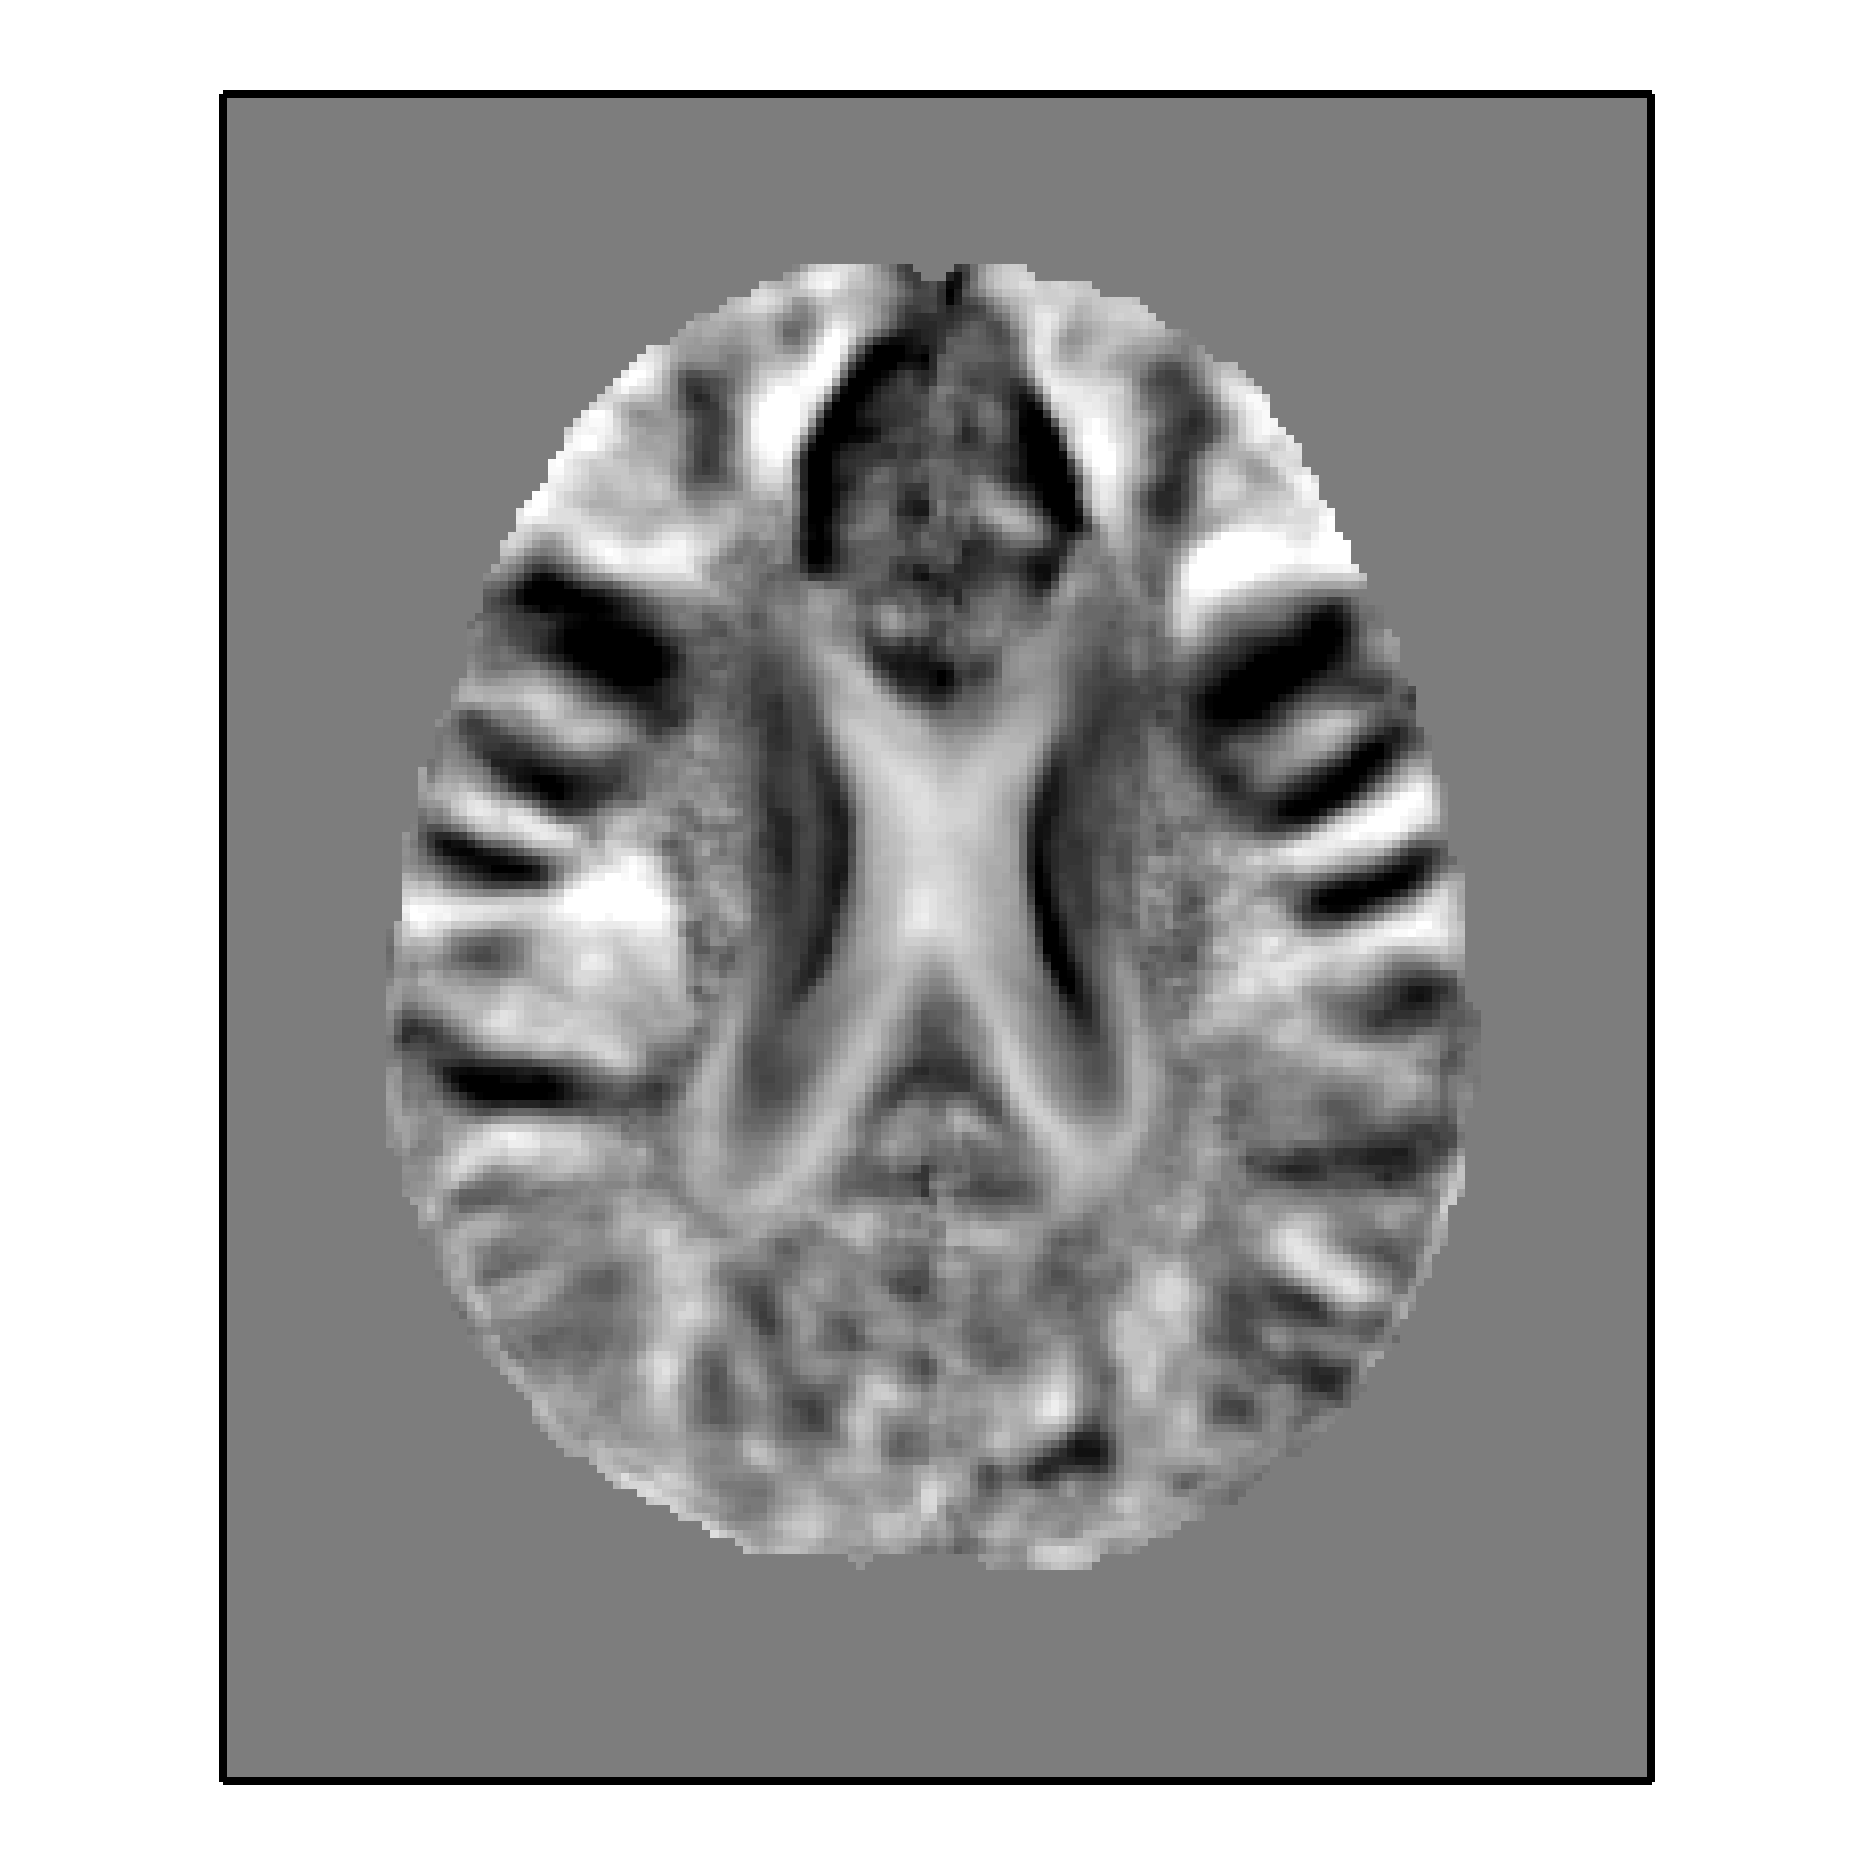

We also use principal component analysis (PCA to incorporate more of the voxel intensity value while keeping the dimensionality to a minimum. We adopt a strategy well-known for person identification from facial images, where principal components are computed from a set of headshots; the resulting principal components are often referred to as ’eigenfaces’ [10]. Similarly, we compute ’eigenbrains’ for the entire dataset, and consider the component coefficients resulting from OLS projection of each subject onto the eigenbrain basis set. We compute eigenbrains for two separate slices, one axial slice and one coronal slice (figure 1), selecting slices on which gray matter and white matter volume have been shown to correlate with impaired cognitive ability [11]. We select PCA components by parametrically testing the classifers; the combination of coronal and axial components (#4 and #7, respectively) that maximize test accuracy are shown in figure 1.